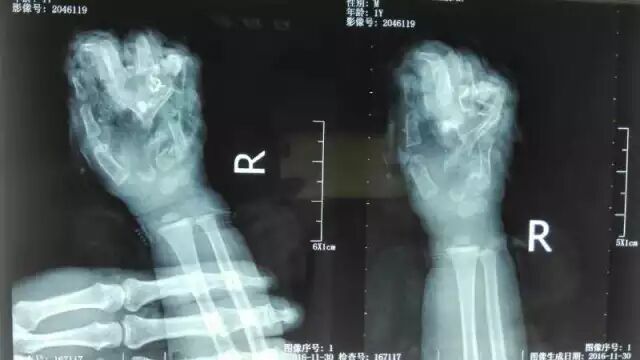

据介绍,小孩大约一岁多。破拆钢板完毕后,消防人员在医护人员的协同下将小孩的手取出,小孩右手的手掌指关节不幸被绞到。

从医院获悉,小孩大约在事发当晚8时许被送到医院,伤势严重。